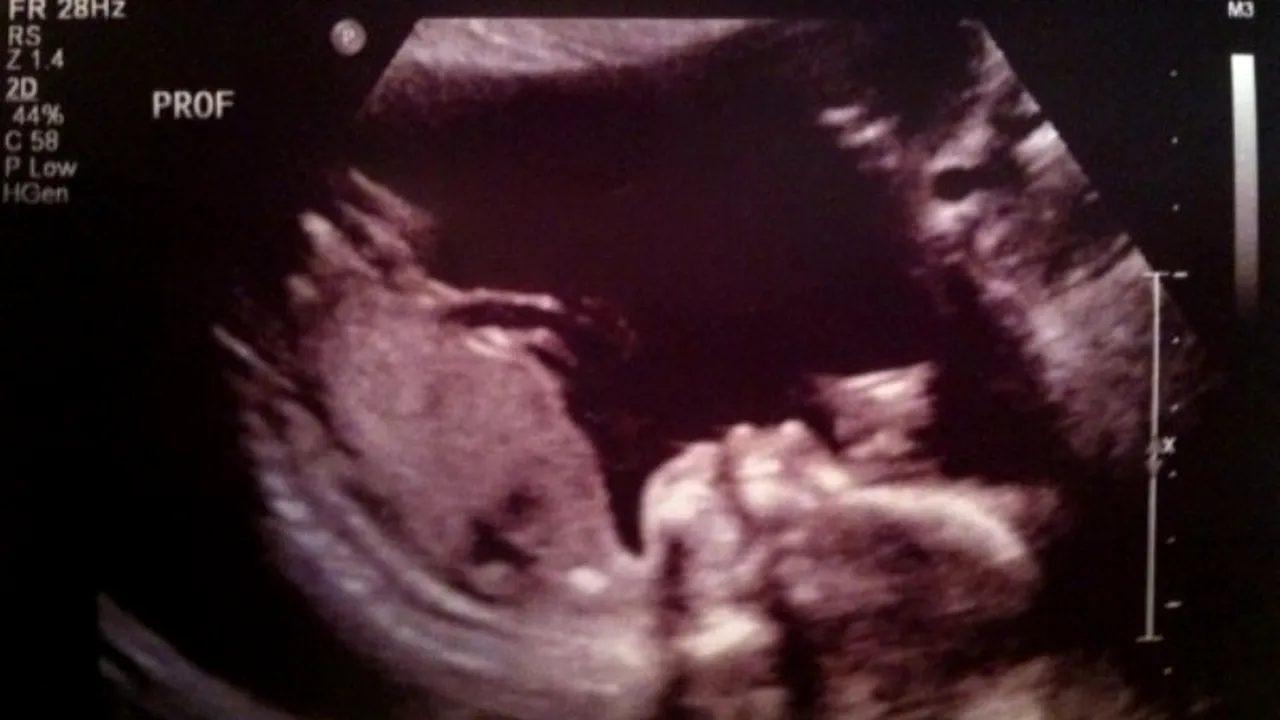

O tânără gravidă din SUA a avut parte de o surpriză incredibilă atunci când a mers la ecografie împreună cu soțul ei.

Împreună cu soțul ei, femeia a observat că, pe lângă bebelușul încă nenăscut, în imagine mai părea să fie ceva.

După ce s-au uitat mai bine la ecogratie, cei doi soți au văzut în partea dreaptă a imaginii chipul unei pisici.

„Eu și soția mea așteptăm primul nostru copil și se pare că și o pisică”, a scris viitorul tată alături de imaginea pe care a publicat-o pe Internet, amuzat de iluzia optică.